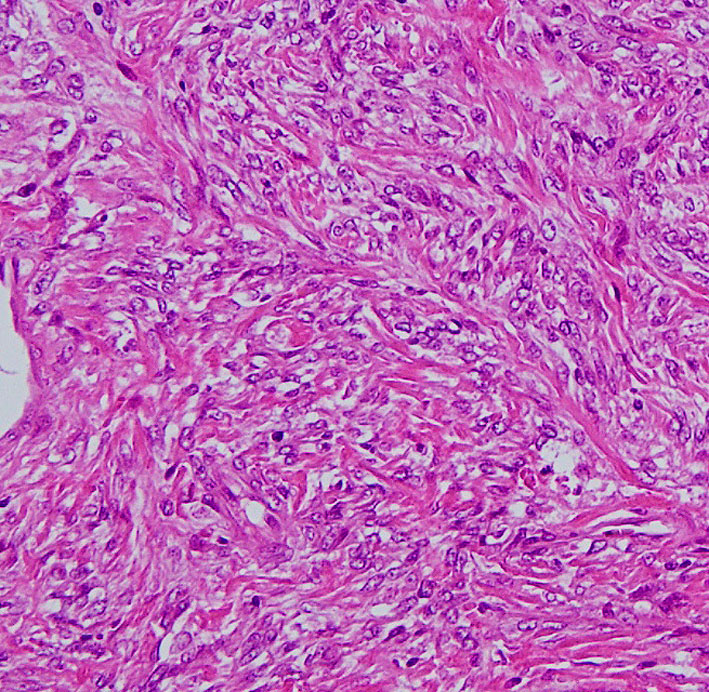

右中頭蓋窩から側頭下窩に抜けた,三叉神経鞘腫と誤診しやすいSFTです。dense collagen fiber の中に,核内空胞を有する異型細胞が密に増殖しています。MIB-1染色が10%程度と高いSFTでGrade IIb SFTと分類されるものです。

この例は,膠原線維 collagenous tissueのなかに紡錘形の核を有する細胞 spindle cell が見られます。核の大小不同は見られますが,上の例よりはグレードが低いと捉えられます。しかし,この例のように一見グレードが低いと思われる例でも髄液播種や全身転移を生じることがあります。

- 病理診断では,Spindle cells are disposed in fascicles between prominent, eosinophilic bands of collagen.と表現されます

- 単調な組織構造を示し,patternless patternとも表現されます

- 膠原線維が多く細胞密度が低いものは本当の良性のグレード1です

- HE染色では,fibromaやmyxomaと鑑別ができないことがあります

- グレード2以上では髄膜腫より高い細胞密度と特有の血管構築 (staghorn vasculature, slit-like vascular channels)がみられます